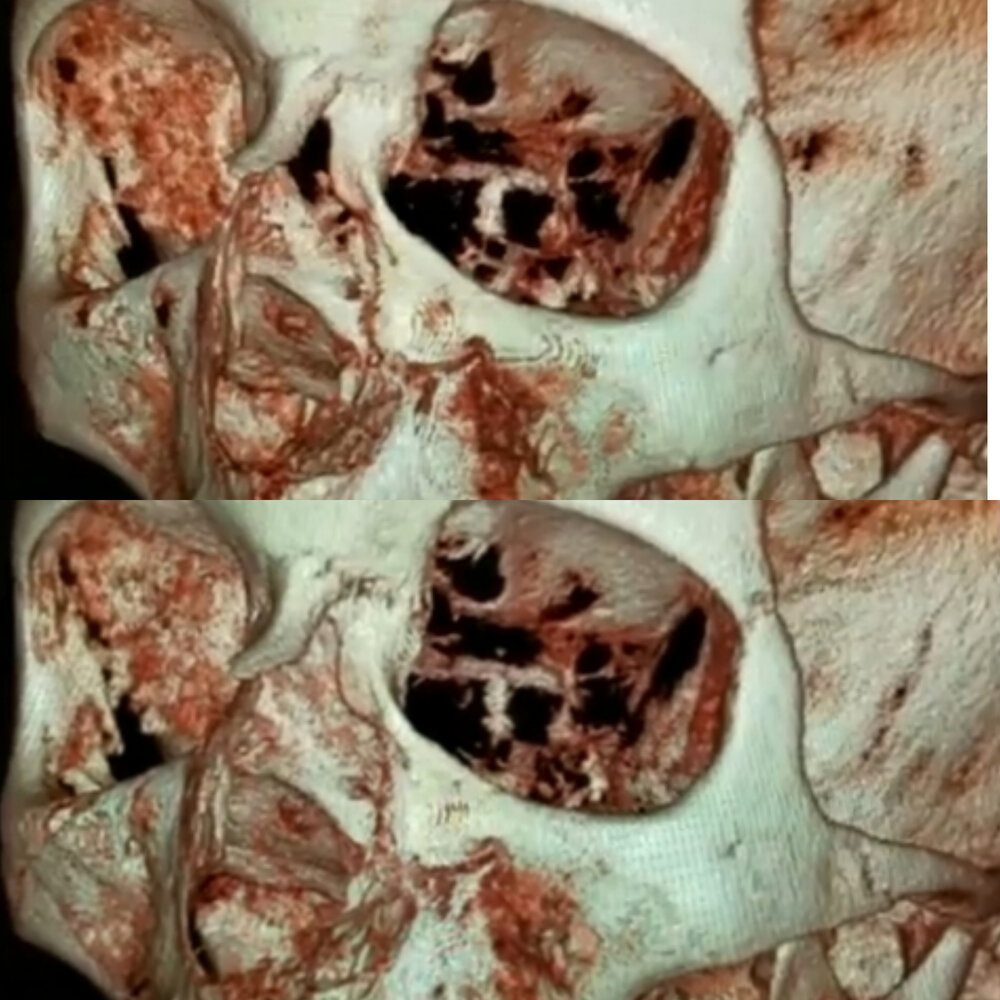

If we take these two pictures of before and after MSE:

And we line them up properly, you can see a very minimal impact on the cheekbone:

Now this is unlikely to be noticeable in real life, unless you're specifically observing the cheekbones. Therefore you shouldnt get MSE just because you want wider cheekbones.

If you look at the diastema, it looks like there has been maybe 6mm of expansion.

So if you go up to 10mm expansion, cheekbone results may be satisfactory. But it's unlikely you will find someone to give you 10mm expansion unless you're palate is tictac tier